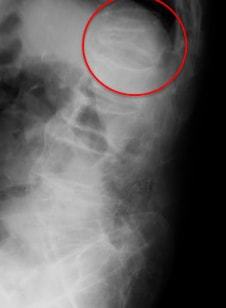

半年程前に耕運機から転落し、第1腰椎圧迫骨折で他院にて3週間入院していました。

術後1週目で抜糸・レントゲン撮影を行い、骨や術創部の状態を確認した上で異常もみられなかったため、予定通り術後8日目での退院となりました。

経皮的椎体形成術により下の写真の様に姿勢の改善が期待できます。